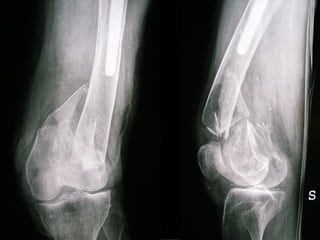

A B C Distal femoral fractures type C Choosing the right strategy and the right implant

INDICAZIONI COMUNI Fratture sovracondiloidee Fratture intercondiliodee Fratture diafisarie distali PARTICOLARI Fratture con grave osteoporosi Fratture periprotesiche